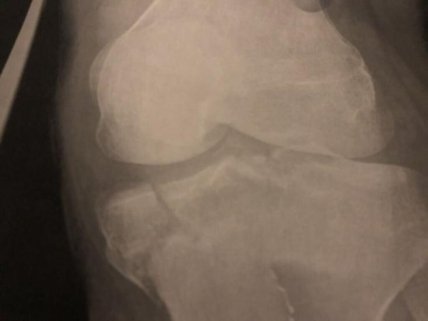

Как оказалось, при этом он сломал две кости ноги, а потому ему пришлось ждать помощи спасателей.

Пострадавшему сообщили в больнице, что его нога будет заживать еще пару несколько недель, а потому об опасных приключения на время придется забыть.